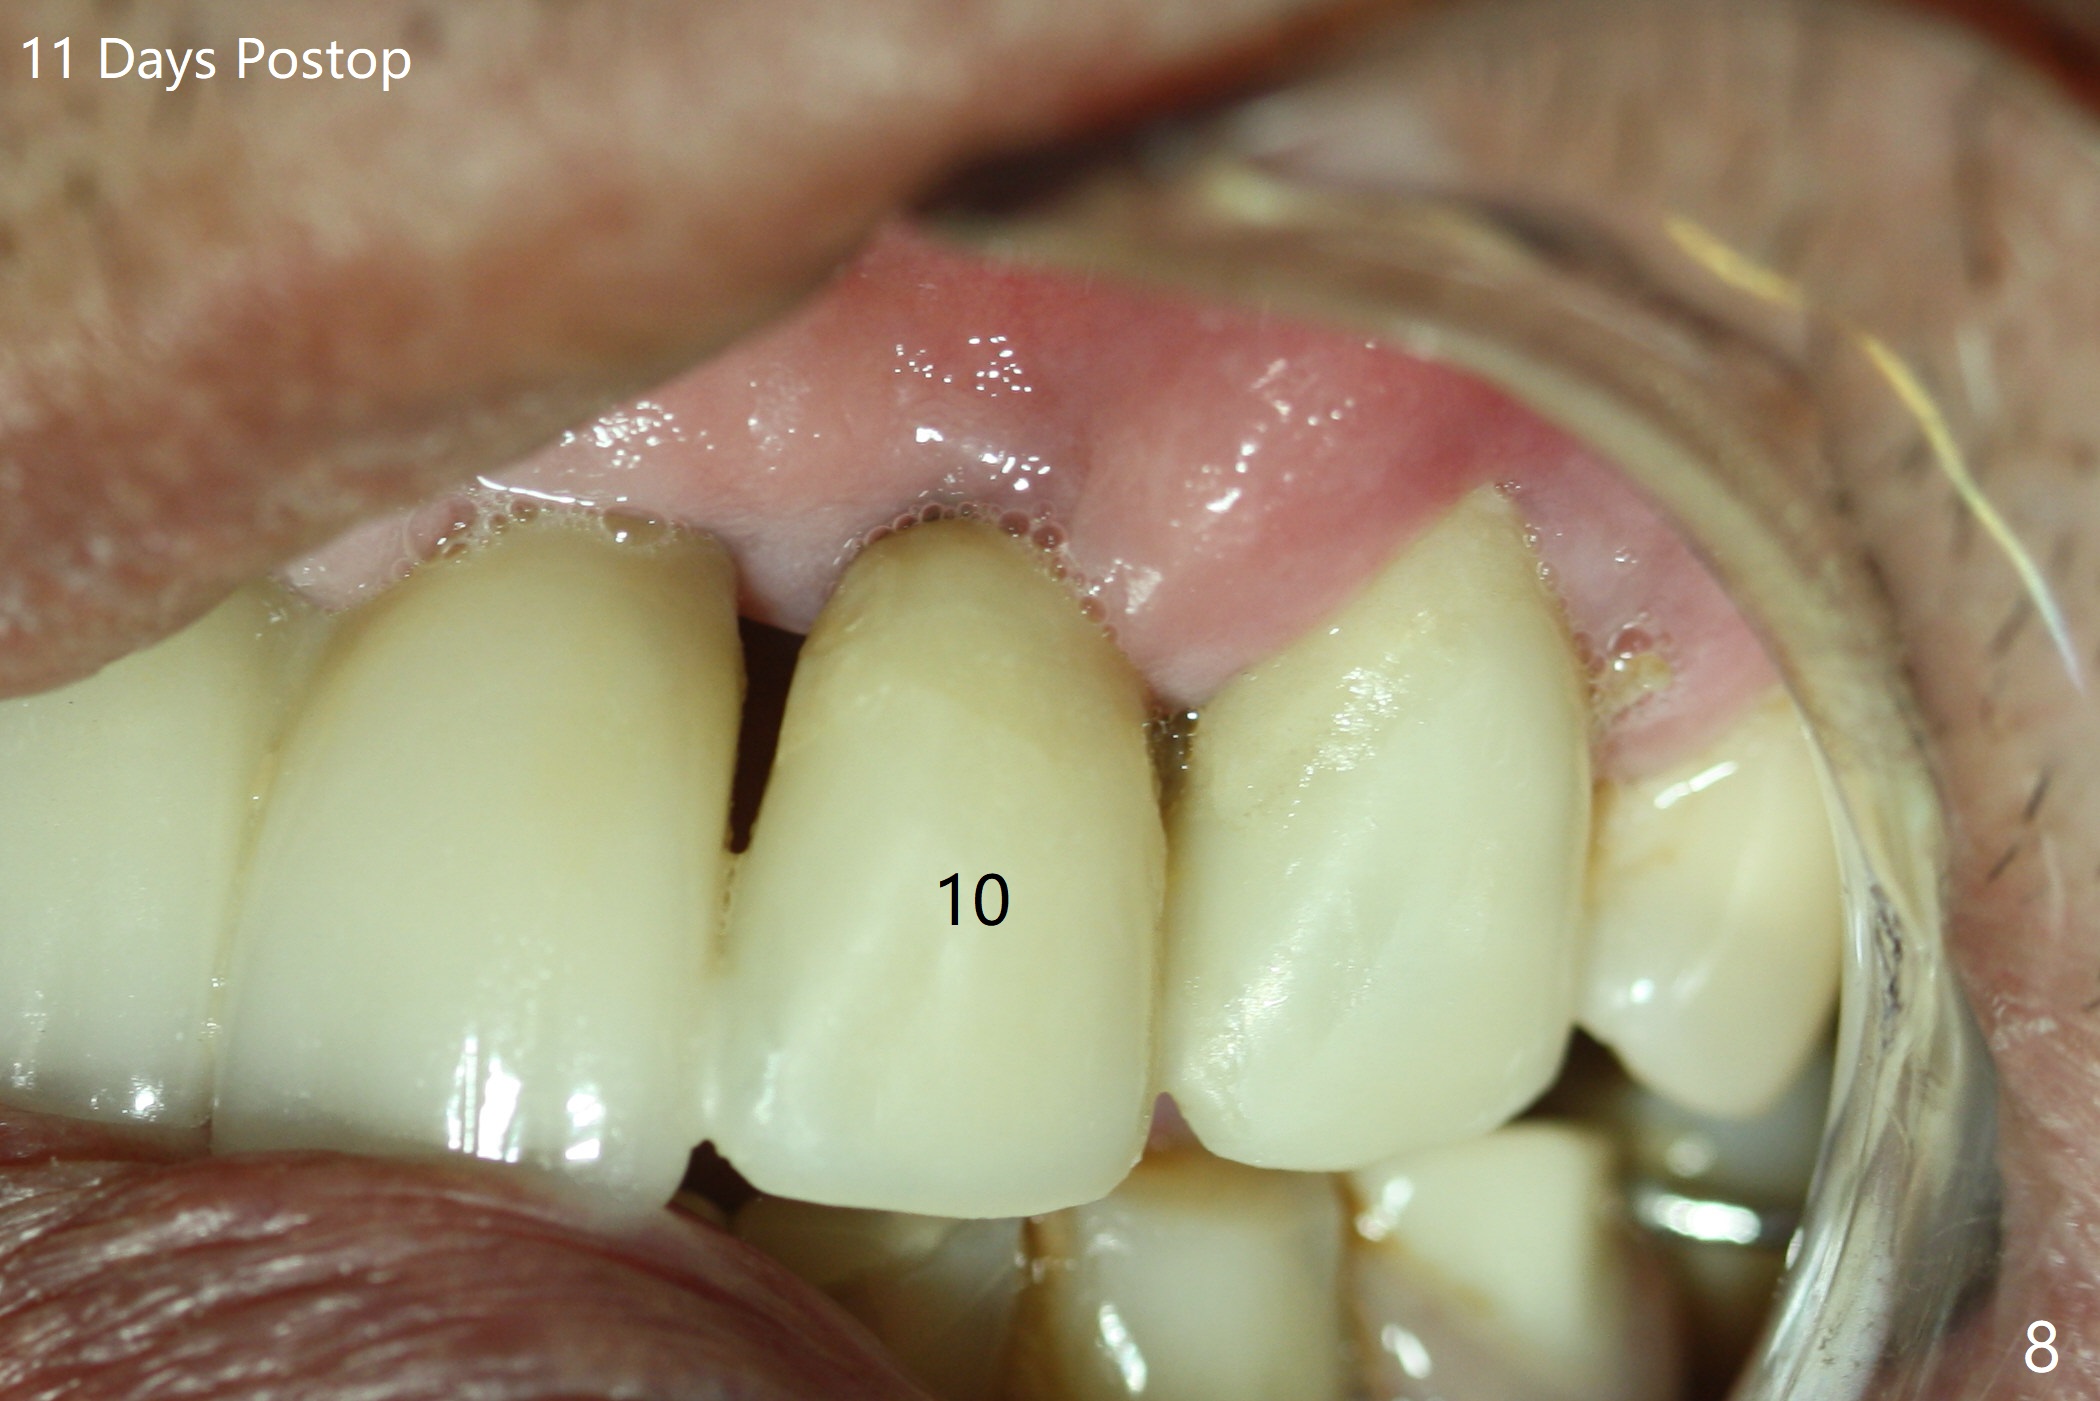

The buccal plate at #10 undergoes atrophy 9 months post immediate implant (Fig.1 *). To prevent the same post-extraction complication at #11, a technique called socket shield is going to be adopted. The buccal portion of the root (Fig.2-6 R, half-moon shaped) remains in place while a 3.5x13 mm implant is placed in the palatal portion of the socket (>50 Ncm). In fact the root is trimmed slightly subcrestal (Fig.6 C). It is assumed that there will be no or minimal bone resorption as long as the periosteum between the buccal plate and the remaining buccal root is not disturbed after tooth removal. After placement of a 4.5x15 degrees A (2mm) angled abutment and Vanilla graft (Fig.7 *), an immediate provisional is fabricated (using a central incisor crown form for #10 because of extra wide space of #11, Fig.8). There is no buccal plate atrophy at the canine 11 days postop (Fig.9). There is smooth transition from the grafted bone to the native bone 4.5 months postop (Fig.10). The buccal plate remains non-atrophic at the canine 4.5 months postop (Fig.11,12). CT taken 1 month post cementation shows that the implants at #10 and 11 are placed somewhat lingually (Fig.13,14 L (*: socket shield)). Gingival swelling is noted (Fig.15 *) with +Bleeding On Probing (^) 8 months post cementation (at the time of #21/24 impression). It appears that the socket shield (Fig.16 S) causes infection and loss of bone graft (*). The shield will be removed with an oblique accessory incision to save the papilla between #10 and 11 (Fig.17 black line). Prepare PRF for sticky bone (x1).